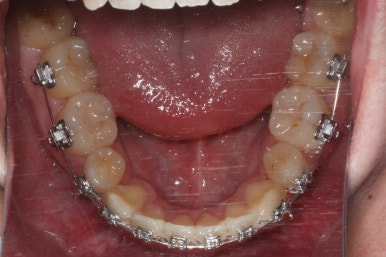

좁아져 있는 위턱뼈를 가로로 넓혀주기 위해서 악궁확장장치를 사용했습니다.

윗니는 선천결손으로 치아가 2개가 모자랐고 앞니도 거꾸로 물리는 상황이여서 아랫니도 균형있게 2개를 추가로 더 뽑았습니다.

악궁확장이 시작될 시점과 악궁확장을 다 진행했을 시점의 비교입니다.

확실히 좁아져 있던 가로 넓이가 넓어진 것을 볼 수 있습니다.

악궁확장장치는 바로 제거할 경우 다시 원상태로 폭이 좁아질 수 있으므로 3~6개월은 유지해야 합니다.

적절한 시기가 되면 악궁확장장치를 제거하고, 확장장치가 걸려있던 치아도 가지런하게 해줍니다.

윗니는 아직 가지런하게 하는 작업 중이며, 아랫니는 가지런하게 하는 작업은 거의 다 되었습니다.

아래 치열은 거의 완료가 되었네요.

이 뽑은 자리도 다 없어졌고요. 대신 윗니는 어금니쪽에 약간의 틈과 기울어진 경사 등등 디테일한 조절을 계속해 나갑니다.